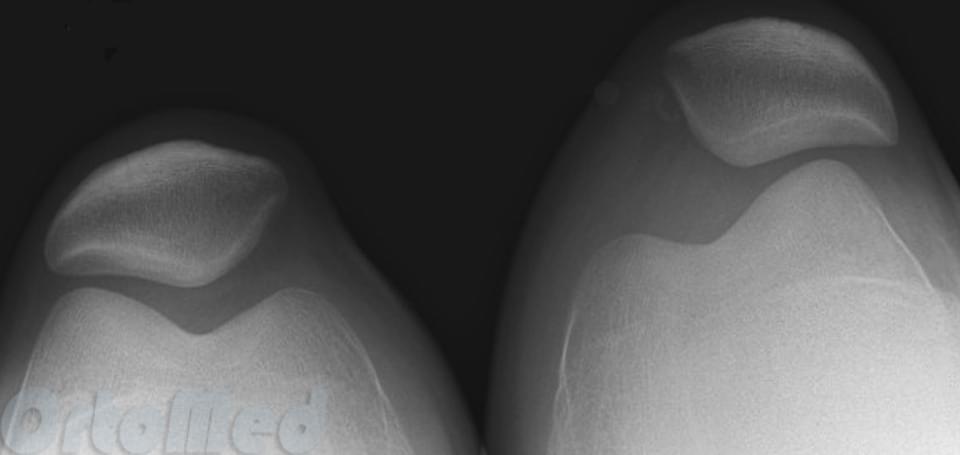

Сверху – боковая рентгенограмма, снизу – аксиальная, на которой видно нормальное взаимоотношение надколенника и бедренной кости

Бывает гиперпрессия коленной чашечки, то есть повышенное давление на суставную фасетку – латеральная гиперпрессия, то есть повышенное давление на наружный мыщелок бедренной кости, медиальная гиперпрессия, то есть повышенное давление на внутренний мыщелок бедренной кости. При латеральной гиперпрессии надколенник давит на наружную фасетку, при ещё большем смещении – появляется подвывих надколенника, при полном смещении – вывих.

Слева – подвывих надколенника, тенденция к смещению кнаружи; справа – вывих надколенника